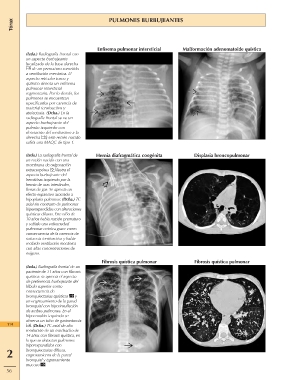

Tórax PULMONES BURBUJEANTES

(Izda.) Radiografía frontal con Enfisema pulmonar intersticial Malformación adenomatoide quística

un aspecto burbujeante Hernia diafragmática congénita Displasia broncopulmonar

localizado de la base derecha Fibrosis quística pulmonar

Fibrosis quística pulmonar

de un prematuro sometido

a ventilación mecánica. El

aspecto reticular tosco y

quístico denota un enfisema

pulmonar intersticial

segmentario. Por lo demás, los

pulmones se encuentran

opacificados por carencia de

material tensioactivo y

atelectasia. (Dcha.) En la

radiografía frontal se ve un

aspecto burbujeante del

pulmón izquierdo con

desviación del mediastino a la

derecha ; este recién nacido

sufría una MAQC de tipo 1.

(Izda.) La radiografía frontal de

un recién nacido con una

membrana de oxigenación

extracorpórea ilustra el

hemitórax izquierdo por la

hernia de asas intestinales,

llenas de gas. Se aprecia un

efecto expansivo asociado a

hipoplasia pulmonar. (Dcha.) TC

axial sin contraste de pulmones

hiperexpandidos con alteraciones

quísticas difusas. Este niño de

10 años había nacido prematuro

y sufrido una enfermedad

pulmonar crónica grave como

consecuencia de la carencia de

sustancia tensioactiva y había

recibido ventilación mecánica

con altas concentraciones de

oxígeno.

(Izda.) Radiografía frontal de un

paciente de 11 años con fibrosis

quística: se aprecia el aspecto

de preferencia burbujeante del

lóbulo superior como

consecuencia de

bronquiectasias quísticas y

un engrosamiento de la pared

bronquial con hiperinsuflación

de ambos pulmones. En el

hipocondrio izquierdo se

observa un tubo de gastrostomía

114 . (Dcha.) TC axial de alta

resolución de un muchacho de

14 años con fibrosis quística, en

la que se detectan pulmones

hiperexpandidos con

2 bronquiectasias difusas,

engrosamiento de la pared

bronquial y taponamiento

mucoso .